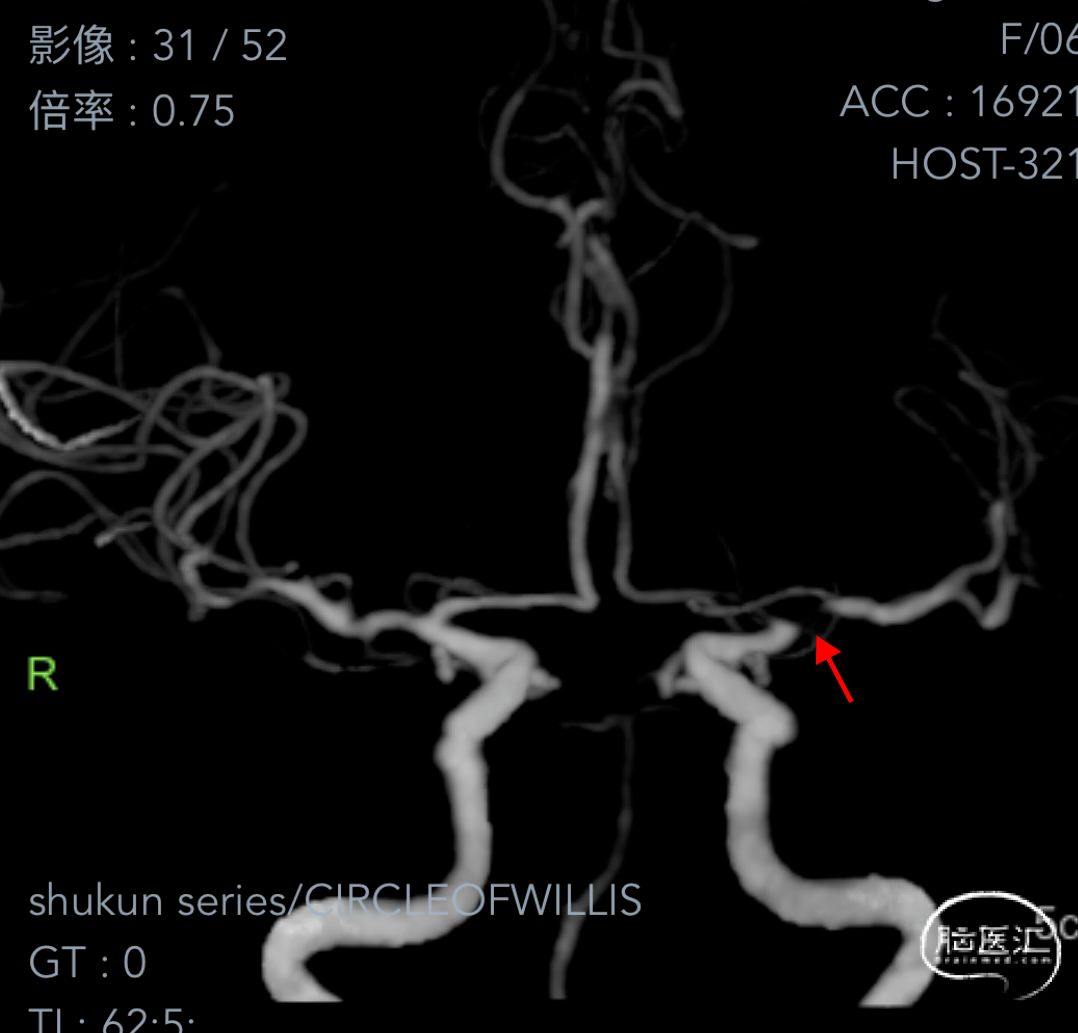

➤2024.3.20 CTA

左侧大脑中动脉M1段起始部重度狭窄。

➤经股动脉入路造影影像

II型弓,左侧大脑中动脉M1段重度狭窄(几近闭塞)。

沿微导丝将赛诺NOVA®颅内药物洗脱支架 2.5*15mm送至左侧大脑中动脉狭窄段,造影定位准确。